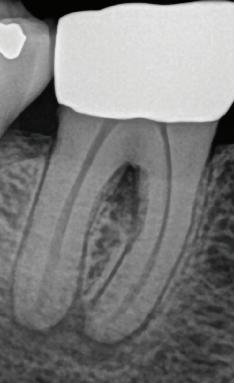

EdgePRO®

Cleaning. Enhanced.

Provides outstanding Cleaning, Debridement and Disinfection by removing infected tissue, biofilm and smear layer killing up to 99% of bacteria commonly found in the root canals. (1,2,3,4) This should give you the confidence you need to treat even the most complex anatomies.

Endodontics. Streamlined.

Lets “You be You”– shape and obturate the canals the way you want without the need to change your technique. EdgePRO™ offers the potential for streamlined workflow and one-visit treatment resulting in reduced treatment time and patient visits.

Technology. Affordable.

Has state-of-the-art technology at more affordable pricing that is as low as 1/3 the cost of other irrigation devices. EdgePRO™ gives your practice access to the future of Endodontics and an edge in winning more referral business.